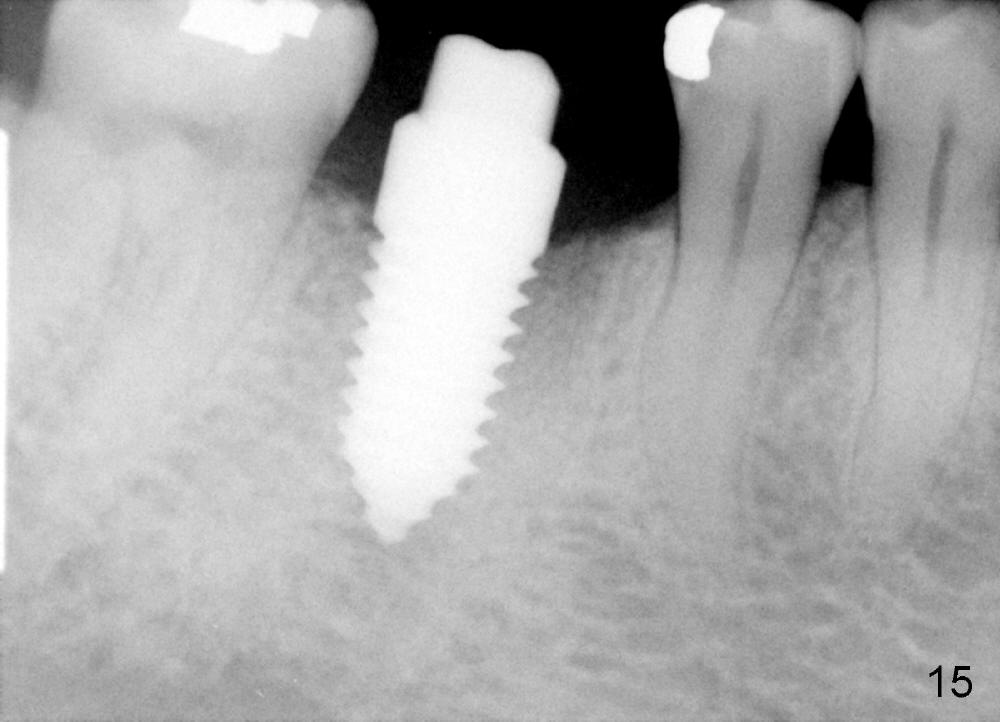

A 38-year-old lady agrees to have implant placement 7 years after loss of the crown of the lower right first molar (Fig.1,2). When the tooth is extracted, the septum is found to be low (Fig.3,4). To confirm it, a PA is taken (Fig.5). To initiate an osteotomy in the septum, it is trans-sectioned with thin osteotomes as shown in Fig.4 insert (black line). A 2 mm pilot drill is placed in the septum (Fig.6: P). The osteotomy is enlarged by 2.5-4.0 mm reamers (Fig.7,8), followed by insertion of 6x17 mm tapered tap at the depth 14 mm (Fig.9). The osteotomy is further enlarged by 4.5 and 5.0 mm reamers. A 6.0x14 mm one piece implant is placed initially. The trajectory is not ideal. A 6.0x14 mm one piece implant is placed initially. The trajectory is not ideal. The implant is removed from the osteotomy partially and reinserted with improved trajectory (Fig.11, compare to Fig.10 (red line)). Primary stability is high. There is not much bone mesiodistally so that the trajectory is easily changed in that direction. After abutment preparation, mixture of autogenous bone (harvested from reamers) and allograft is placed in the residual mesial and distal sockets (Fig.12). To contain the bone graft, an immediate provisional is placed (Fig.13 P). The occlusal plane of the provisional is significantly lower than that of the adjacent teeth to avoid micromovement of the implant. The patient is advised to eat soft food on the left side. Six days postop, the patient returns for prophy. The provisional is removed; the bone graft appears to be incorporating into the socket (Fig.14). After recementation, the provisional remains in place for 3.5 months; PA shows increased bone density in the mesial and distal sockets (Fig.15, compare to Fig.5,11). Due to insurance coverage, the patient defers fabrication of definitive restoration for at least 7 months. The immediate provisional is finally lost 8.5 months postop: the gingiva attaches to the 1-piece implant (Fig.16), while the density of the mesial socket increases (Fig.17 *) with formation of the cortex (lamina dura) coronally (v). Before the provisional (Fig.18 P) is removed for cementation of the definitive restoration, black shadow (*) is noted over the buccal gingiva. It is partially due to buccal placement (Fig.19) and partially due to buccal atrophy over a period of 10.5 months postop. How to prevent buccal placement? Positioning the first pilot drill in the septum buccolingually is a key. Eleven months post crown (Fig.20 C) cementation, the black shadow remains, but there is no tenderness. If the implant threads are immediately underneath the periosteum, there is tenderness.